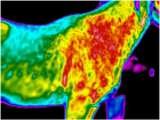

Wirbelblockaden können mit der thermografischen Diagnostik sichtbar dargestellt werden. Blockierte Wirbel werden behandelt und anschließend mit der Matrix-Rhythmus-Therapie weiter therapiert.

Wirbelblockaden sichtbar dargestellt mit Thermografie Diagnostik

Durch eine bestehende Blockade im linken HWS - Bereich, wurde die rechte Halsseite muskulär überstrapaziert. Folglich entstanden Folgeprobleme mit Einschränkung in diesem Segment. Mit Hilfe der Thermographie kann das Ausmaß einer Entzündung im Verlauf des Muskela beurteilt werden. Folglich entstanden dadurch Blockaden. Eineosteopathische Untersuchung erfolgte, zur weiteren Behandlung wurde dieMatrix-Rhythmus-Therapie eingesetzt.

Damit sich die Weichteilstrukturen an die neue Funktion gewöhnen konnten um die neue Funktion wieder aufrecht zu erhalten. Ansonsten würde der Körper wieder in seine alte Funktionsstörung zurück fallen und die Störungen treten erneut wieder auf.